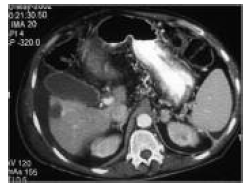

Figure 3 and 4. Computed Tomography Images Demonstrate Exact Placement of Radiofrequency Needle